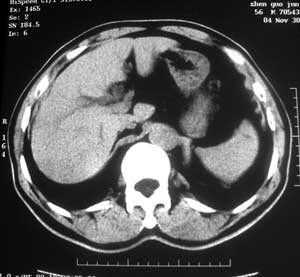

患者,男,57岁,梗阻性黄疸10余天。

这个病例胰头无明显增大,胆总管扩张明显而肝内胆管扩张更不明显,病程较短,

注意到十二指肠乳头明显突出,但尚光滑。分析以下可能性:

1、十二指肠乳头本身的病变,如乳头炎症;

2、急性乳头水肿,胆总管下端结石排石后乳头水肿;

3、壶腹部胆总管下端肿瘤累及十二指肠乳头。

十二指肠乳头粘膜慢性非特异性炎症